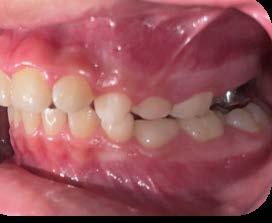

Entre los elementos que conforman al sistema estomatognático, están los dientes caninos, órganos dentales esenciales en la fisiología masticatoria; punto de unión y continuidad estética entre la línea de la sonrisa y el corredor posterior del arco dental, además de que ejercen la función de pilares estabilizadores en la oclusión fisiológica (Figura 1).

Los caninos son indispensables durante los movimientos de lateralidad y vitales para la continuidad de los arcos dentales, tanto en la dentición decidua como en la permanente; son responsables del funcionamiento y la armonía oclusal. Su posición adecuada en el arco asegura un buen contorno de la cara, sonrisa agradable y armónica con la estética facial. (Figura 2).

El canino divide su cara vestibular en 2 vertientes, una mesial que se continúa con los incisivos y otra distal que se alinea con los dientes posteriores, razón por la cual su ausencia genera alteraciones muy importantes en la oclusión y la estabilidad fisiológica del sistema estomatognático (Figura 3).

La incidencia de inclusión en los caninos superiores e inferiores tiene diferentes etiologías y similitudes. En ambos casos, el motivo principal se deriva de razones propias por su anatomía, tamaño en volumen coronal y largo de la raíz; sumado a esto, su ubicación lejana intraósea respecto al arco dental, desde la germinación y/o inicio de formación y desarrollo y, hasta alcanzar la erupción (Figura 4).